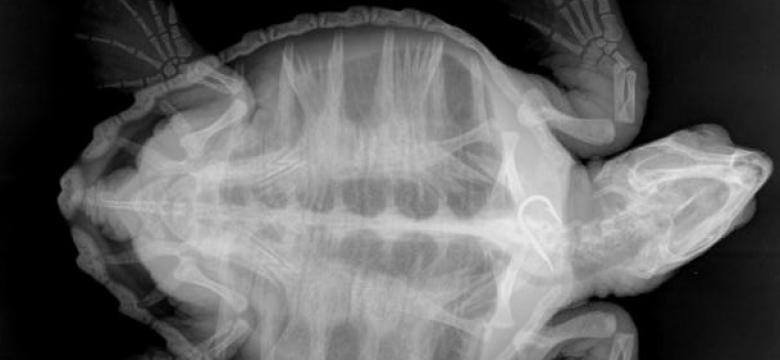

Guardiamoci dentro

In alcuni casi la radiologia si avvale dell’impiego di mezzi di contrasto per visualizzare immagini altrimenti “radiotrasparenti”, per evidenziare meglio alcune lesioni, il percorso di vasi o delle vie urinarie. In diverse occasioni in campo veterinario l’esame radiografico viene eseguito su pazienti in stato di sedazione. Questo perché per ottenere immagini di qualità elevata è necessaria l’immobilità assoluta dell’animale il cui corpo deve essere posizionato secondo protocolli ben precisi e di difficile realizzazione in stato di veglia. A tale scopo la sala radiologica del nostro ambulatorio è dotata anche di impianto di anestesia gassosa.